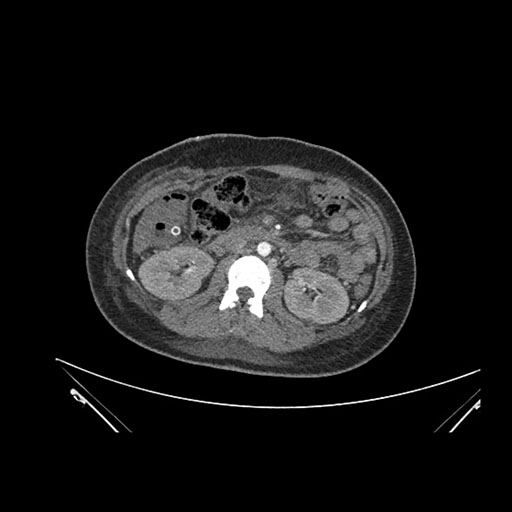

Look through the patient's CT scan to identify any areas of concern for the necessary procedure.

Axial Arterial

Axial Venous

Imaging analysis

Based on initial findings, which issue(s) would you be most concerned about?